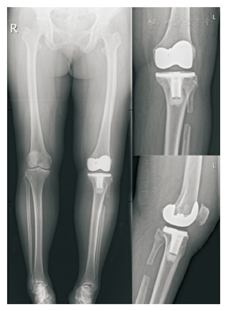

术后患者双下肢站立位全长位片见图4,术后对患者进行常规对症治疗及相关的康复训练,术后第2天即拔除负压引流,患者下地行走。术后19 d拆线出院,出院时患者VAS评分3分,同时记录出院时患者WOMAC问卷、KSS膝关节评分、Lysholm膝关节评分、SF-36生活质量评分(各项均较入院时有改善)(表1)。患者于2018年10月30日至我院骨科门诊复诊,VAS评分1分,WOMAC问卷、KSS膝关节评分、Lysholm膝关节评分等结果见表1,SF-36生活质量评分各项较出院时有改善,较入院时改善明显,站立位及最大下蹲位状态见图5。目前患者仍在随访中。

杨延江等通过解剖学提出"弓弦理论"假说,将骨性结构比作是"弓",外侧肌肉、韧带等软组织看作为"弦";在截骨术前,腓骨头与胫骨外侧髁之间连接紧密,活动度很小,此时"弦"较长,不能拉紧而张力较低;而在截骨术后,比目鱼肌和腓肠肌等小腿肌肉将腓骨向远端牵拉,"弦"拉紧,形成以胫骨平台外侧为支点的一个杠杆结构,撬起股骨内踝,使平台内侧张力减低,膝关节的负重从内侧平台转移向外侧平台,使股骨下端的机械轴重新排列,从而解除内侧间室的骨关节炎症状[15]。腓骨近端截骨术后,腓骨近端与截骨远端失去连续性,外侧副韧带和髂胫束分支紧张,施予外展的力,股二头肌收缩产生斜向后上方的前拉力,上述力量通过腓骨近端、上胫腓联合作用于胫骨近端,可使胫腓骨外旋、外展,术后X线片可显示腓骨近端截骨端外展(图2、图4)。因此在截骨时要注意,若截骨平面过高,腓神经损伤风险增大,肌肉对腓骨截骨近端向下牵拉作用减小,同时受股二头肌的收缩影响,腓骨头对胫骨外侧支撑作用可能仍然存在;若截骨平面较低,近端留置过长,骨间膜及腓骨周围软组织对腓骨近段稳定作用处于优势地位,可阻碍腓骨头下沉,对抗肌肉对腓骨头的向下牵拉作用,不利于胫骨外侧柱的沉降,术后可能对膝关节内侧疼痛的缓解程度不明显[16]。